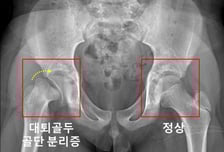

외상없었는데 허벅지뼈 분리? 호르몬 3개 부족하면 발병률 744배↑

허벅지뼈(대퇴골)의 윗부분을 대퇴골두라 한다. 외상을 입지 않았는데도 대퇴골두가 분리되는 질환이 '대퇴골두 골단 분리증'이다. 주요 원인으로 내분비질환이 꼽히는데, 내분비질환을 앓는 소아청소년 환자에서의 대퇴골두 골단 분리증의 발병률을 한국 연구진이 세계 최초로 규명했다. 서울대어린이병원 신창호 교수·이윤정 교수 공동 연구팀(황성현 전문의)은 국민건강보험공단 데이터를 활용해 내분비질환 환자 8만769명과 대퇴골두 골단 분리증 환자 191명을 14년간 추적 관찰한 결과를 20일 발표했다. 허벅지뼈(대퇴골) 위쪽의 성장판 부위에서 대퇴골두와 그 아래 뼈가 특별한 외상이 없는 데도 분리될 때 대퇴골두 골단 분리증으로 진단한다. 진단이 늦어지면 대퇴비구 충돌증후군, 대퇴골두가 썩는 대퇴골두 무혈성 괴사가 발생할 수 있다. 대퇴골두 골단 분리증의 주요 위험 요인으로 '내분비질환'이 꼽힌다. 하지만 기존 연구들에서는 각 내분비질환에 따라 실제 위험도가 얼마나 되는지, 부족한 호르몬 개수에 따